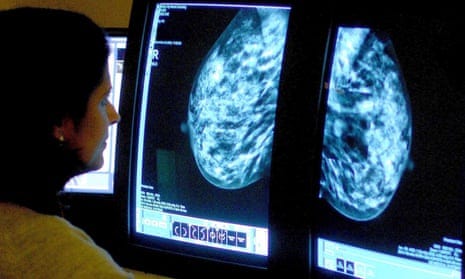

AI in mammography screening is safe and dramatically reduces Radiologist workloads

A.I. use in breast cancer screening as good as two radiologists, study finds

Recently, there was a study with a bit of a milestone. A newly published study in the the Lancet Oncology journal has found that the use of AI in mammogram cancer screening can safely cut radiologist workloads nearly in half without risk of increasing false-positive results.

The broad conclusion is that AI-supported mammography screening resulted in a similar cancer detection rate compared with standard double reading, with a substantially lower screen-reading workload, indicating that the use of AI in mammography screening is safe. The trial was thus not halted and the primary endpoint of interval cancer rate will be assessed in 100 000 enrolled participants after 2-years of follow up.

Breast cancer is the most common cancer among women in the U.S., accounting for about 30 percent of all new cancer cases in women each year. In this article, I detail the study and speculate on how the future of healthcare will mature with more advanced technologies.